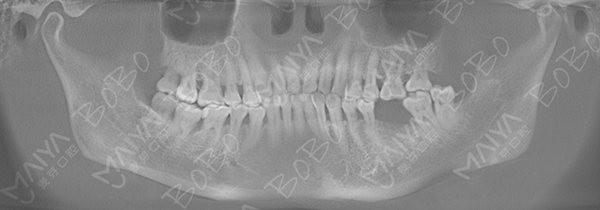

赵阿姨拍摄口腔全景ct

口腔ct全景片